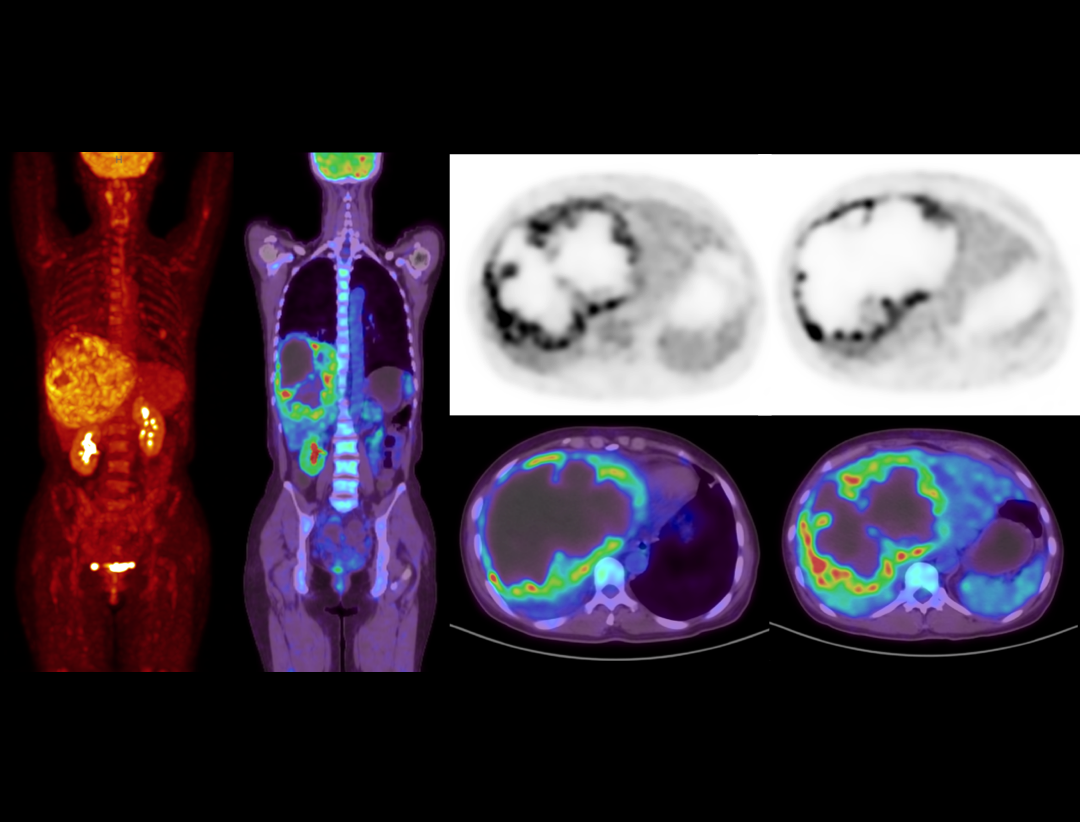

全真数字PET与160层北斗CT强强联手,将高品质的功能影像与解剖学影像精准融合,显著提升微小病灶检测精度,全面助力肿瘤、心脏和神经等重大疾病领域的精准诊疗。

2.9mm NEMA分辨率

硬件源头提升空间分辨率近40%*

*相较于空间分辨率为4mm的PET-CT系统

HYPER Iterative®4D全迭代算法

软件算法保障PET图像高清还原